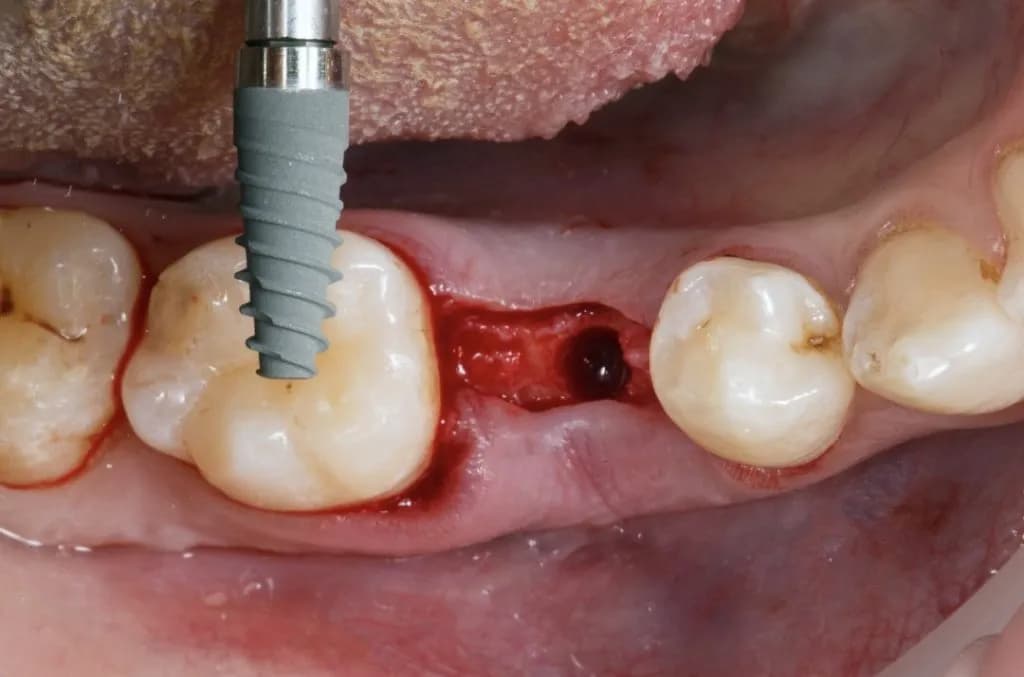

Implantacja natychmiastowa to metoda, która polega na wszczepieniu implantu w tej samej wizycie, co ekstrakcja zęba. Główne zalety tej metody to szybsza regeneracja oraz poprawa estetyki uśmiechu. Aby móc skorzystać z tej opcji, konieczne jest spełnienie kilku warunków. Przede wszystkim, jakość i ilość kości muszą być odpowiednie, a także nie może być stanu zapalnego w okolicy zębodołu.

W przypadku spełnienia tych wymagań, implantacja natychmiastowa może przynieść szereg korzyści, takich jak zmniejszenie potrzeby dodatkowych zabiegów oraz szybsze przywrócenie funkcjonalności zęba. Warto jednak pamiętać, że nie każdy pacjent kwalifikuje się do tego typu implantacji, dlatego konsultacja z lekarzem jest kluczowa.